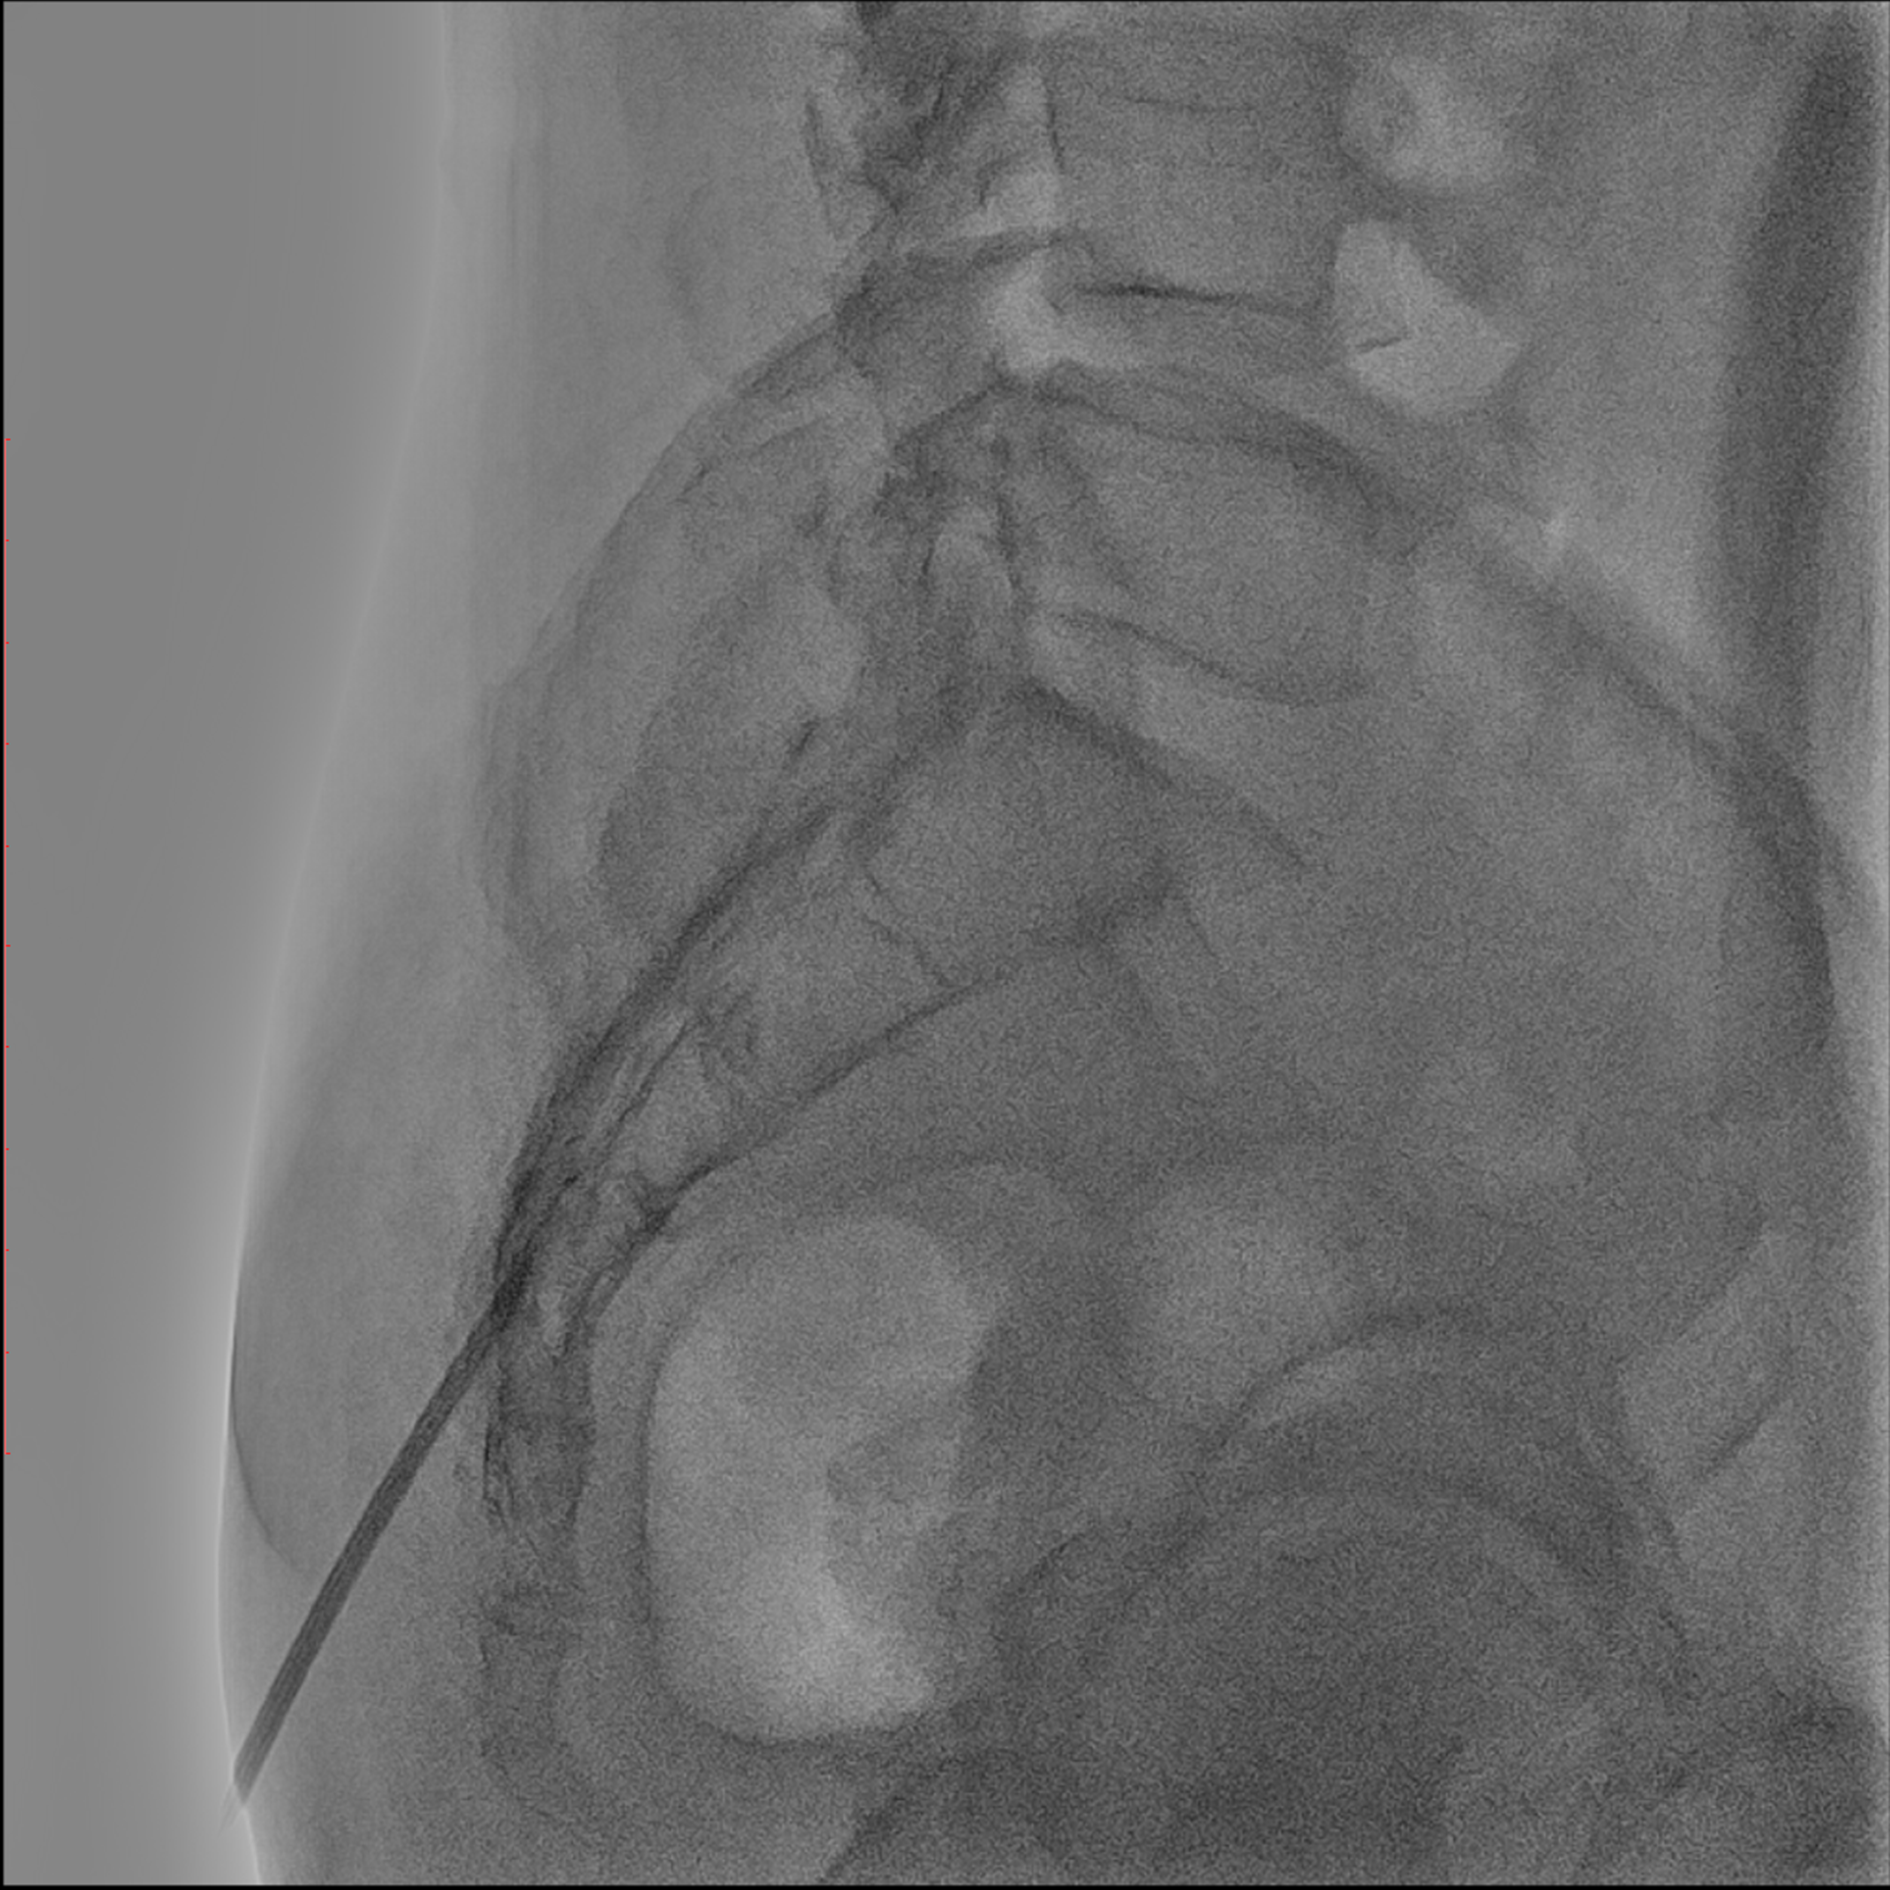

Editorial/Editor's Pick 경막외 유착박리술, Epidural Neuroplasty by Pharmacopuncture Research Lab 2026. 1. 3. 공유하기 게시글 관리 Acupuncture Radiology 관련글 MRI 요양급여의 적용기준 및 방법에 관한 세부사항 MRI 요양급여의 적용기준 및 방법에 관한 세부사항 [신구대조표] Association of AI‑determinedKellgren–Lawrence grade Portable X-ray